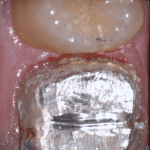

In this clinical video we demonstrate how to scan a molar preparation for the replacement of a crown with recurrent decay and open margins. The molar was root canal treated and the tissue was inflamed. the preparation was imaged and a temporary was fabricated to allow the tissue to heal properly.

The main point of this video is to show how to capture the contacts of the adjacent teeth and the deep marings